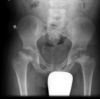

Masculino, 12 anos

Síndrome da sincondrose isquiopúbica assimétrica (Doença de Van Neck-Odelberg)

Variante da normalidade (em geral assintomático)

Crianças

Alargamento e radioluscência na sincondrose isquiopúbica, que simula neoplasias, infecção;